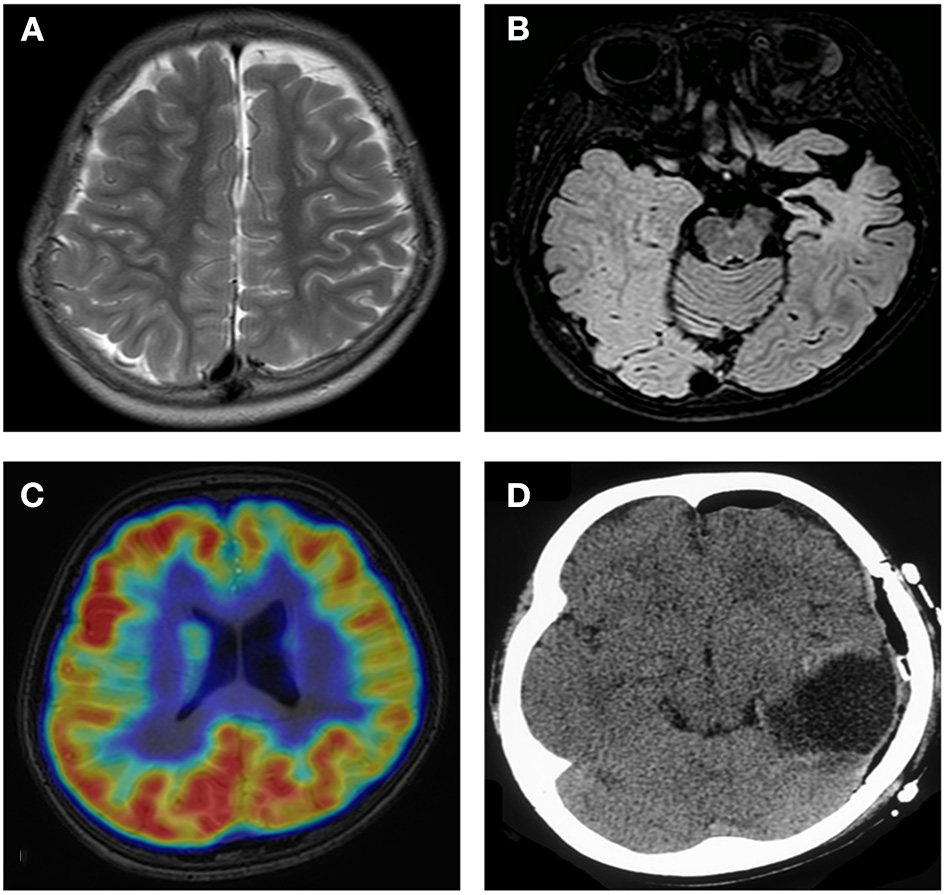

Obvious lesions were observed in the neuroimaging results. In case 1, MRI revealed encephalomalacia located in the right temporal lobe, while abnormal signals were observed in the right parietal and occipital lobes (Figure 2). In case 2, multiple abnormal signals were located bilaterally, with more obvious lesions appearing on the left side (Figure 3). In case 3, MRI showed encephalomalacia mainly in the left temporal, parietal and insular lobes, while mildly abnormal signal was located in the right posterior insular lobe. In case 4, MRI revealed encephalomalacia in the left temporal lobe and mild atrophy in the left hemisphere (Figure 4). PET was performed for three patients (cases 1, 3, and 4). In cases 1 and 3, the hypometabolism seen on PET was concordant with the lesions observed on MRI. In case 4, the extent of hypometabolism on PET was larger than that on MRI.

Figure 2

Neuroimaging data of case 1. MRI reveals encephalomalacia in the right temporal lobe (A). Abnormal signals are observed in the right parietal and occipital lobes (B). PET-MRI Coregistration shows hypometabolism in the temporal, parietal and occipital lobes (C). Postoperative MRI shows disconnection of the temporo-parieto-occipital lobes (D).